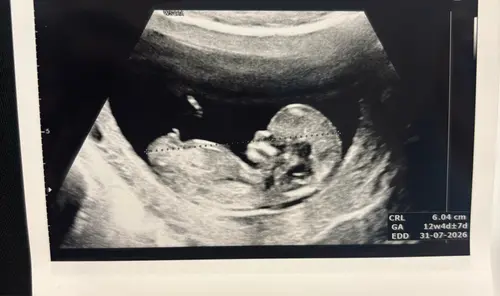

Het ligt misschien aan mij, ik ben geen expert, maar ik denk dat het op deze echofoto moeilijk tot niet te zien is. Ik zie het desbetreffende streepje niet (of ik denk dat het deel uitmaakt van het beentje 🤭). Misschien iemand anders wel? Of heb je een betere foto?

De enige andere 😆